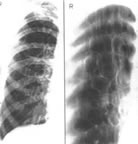

7.胸部X線檢查可呈斑點狀、結節狀或雲絮狀陰影。麴黴球典型的徵象為密度均勻似球狀,其上方有薄壁半月形透亮區,麴黴球可隨體位變動而變動,呈“鐘形陰影”。好發部位為肺上葉.

麴黴球其他輔助檢查:X線上麴黴球表現為肺空洞或胸膜腔內圓形緻密陰影,其邊緣有透光暈影。若空腔較大,尚可見球形陰影有蒂與洞壁相連,形如鐘擺,球形陰影可隨體位變化而改變形態。如果空洞較小,球形病灶填充了大部分空腔,其暈影很小,僅呈一狹長的半月形透亮帶。有學者曾在2例X線平片、體層片和支氣管造影片均無陽性發現的隱源性大咯血患者套用支氣管動脈造影定位後行手術治療,病理髮現1cm左右的細小支氣管囊腫繼發麴黴球。胸部CT檢查特別是高分辨CT的套用為發現細小麴黴球和鑑別診斷提供了有用技術。